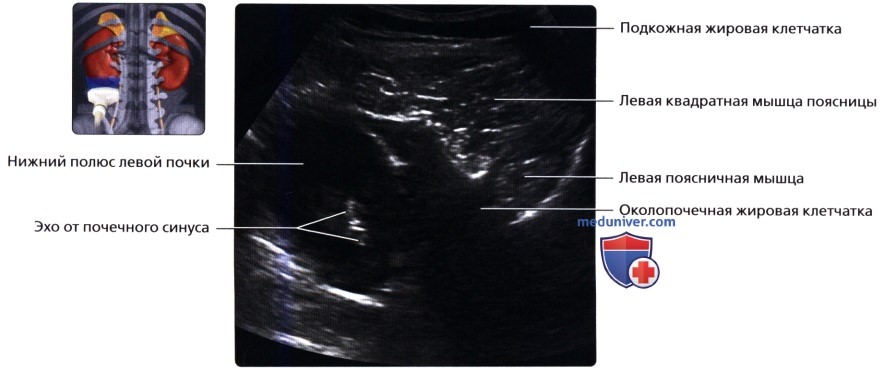

а) Анатомия почек:

2. Топографическая анатомия почки:

• Лежат в забрюшинном пространстве, окружены почечной фасцией (фасция Героты)

• У взрослого каждая почка около 9-14 см в длину и 5 см в ширину

• Обе почки лежат «на» квадратных мышцах поясницы, латеральнее поясничных мышц

б) Лучевая анатомия почки:

1. Обзор:

• Забрюшинные структуры бобовидной формы с четким контуром, смещающиеся при дыхании

в) Особенности визуализации почек:

1. Рекомендации по визуализации:

• Левая почка:

о Ее труднее визуализировать из-за газа в тонкой кишке и в селезеночном изгибе ободочной кишки

о Обычно левую почку проще визуализировать, используя заднебоковой эхографический доступ и попросив пациента немного повернуться вправо приподняв левый бок

о В сложных случаях полностью переверните пациента в положение лежа на правом боку, подложите подушку под его правый бок и попросите его поднять левую руку над головой:

— Для исследования верхнего полюса левой почки можно использовать селезенку как акустическое окно

о Задний эхографический доступ:

— Удобен при инвазивных процедурах (биопсия почки, нефростомия)

— Качество изображения может снижаться из-за теней от околопозвоночных мышц и ребер